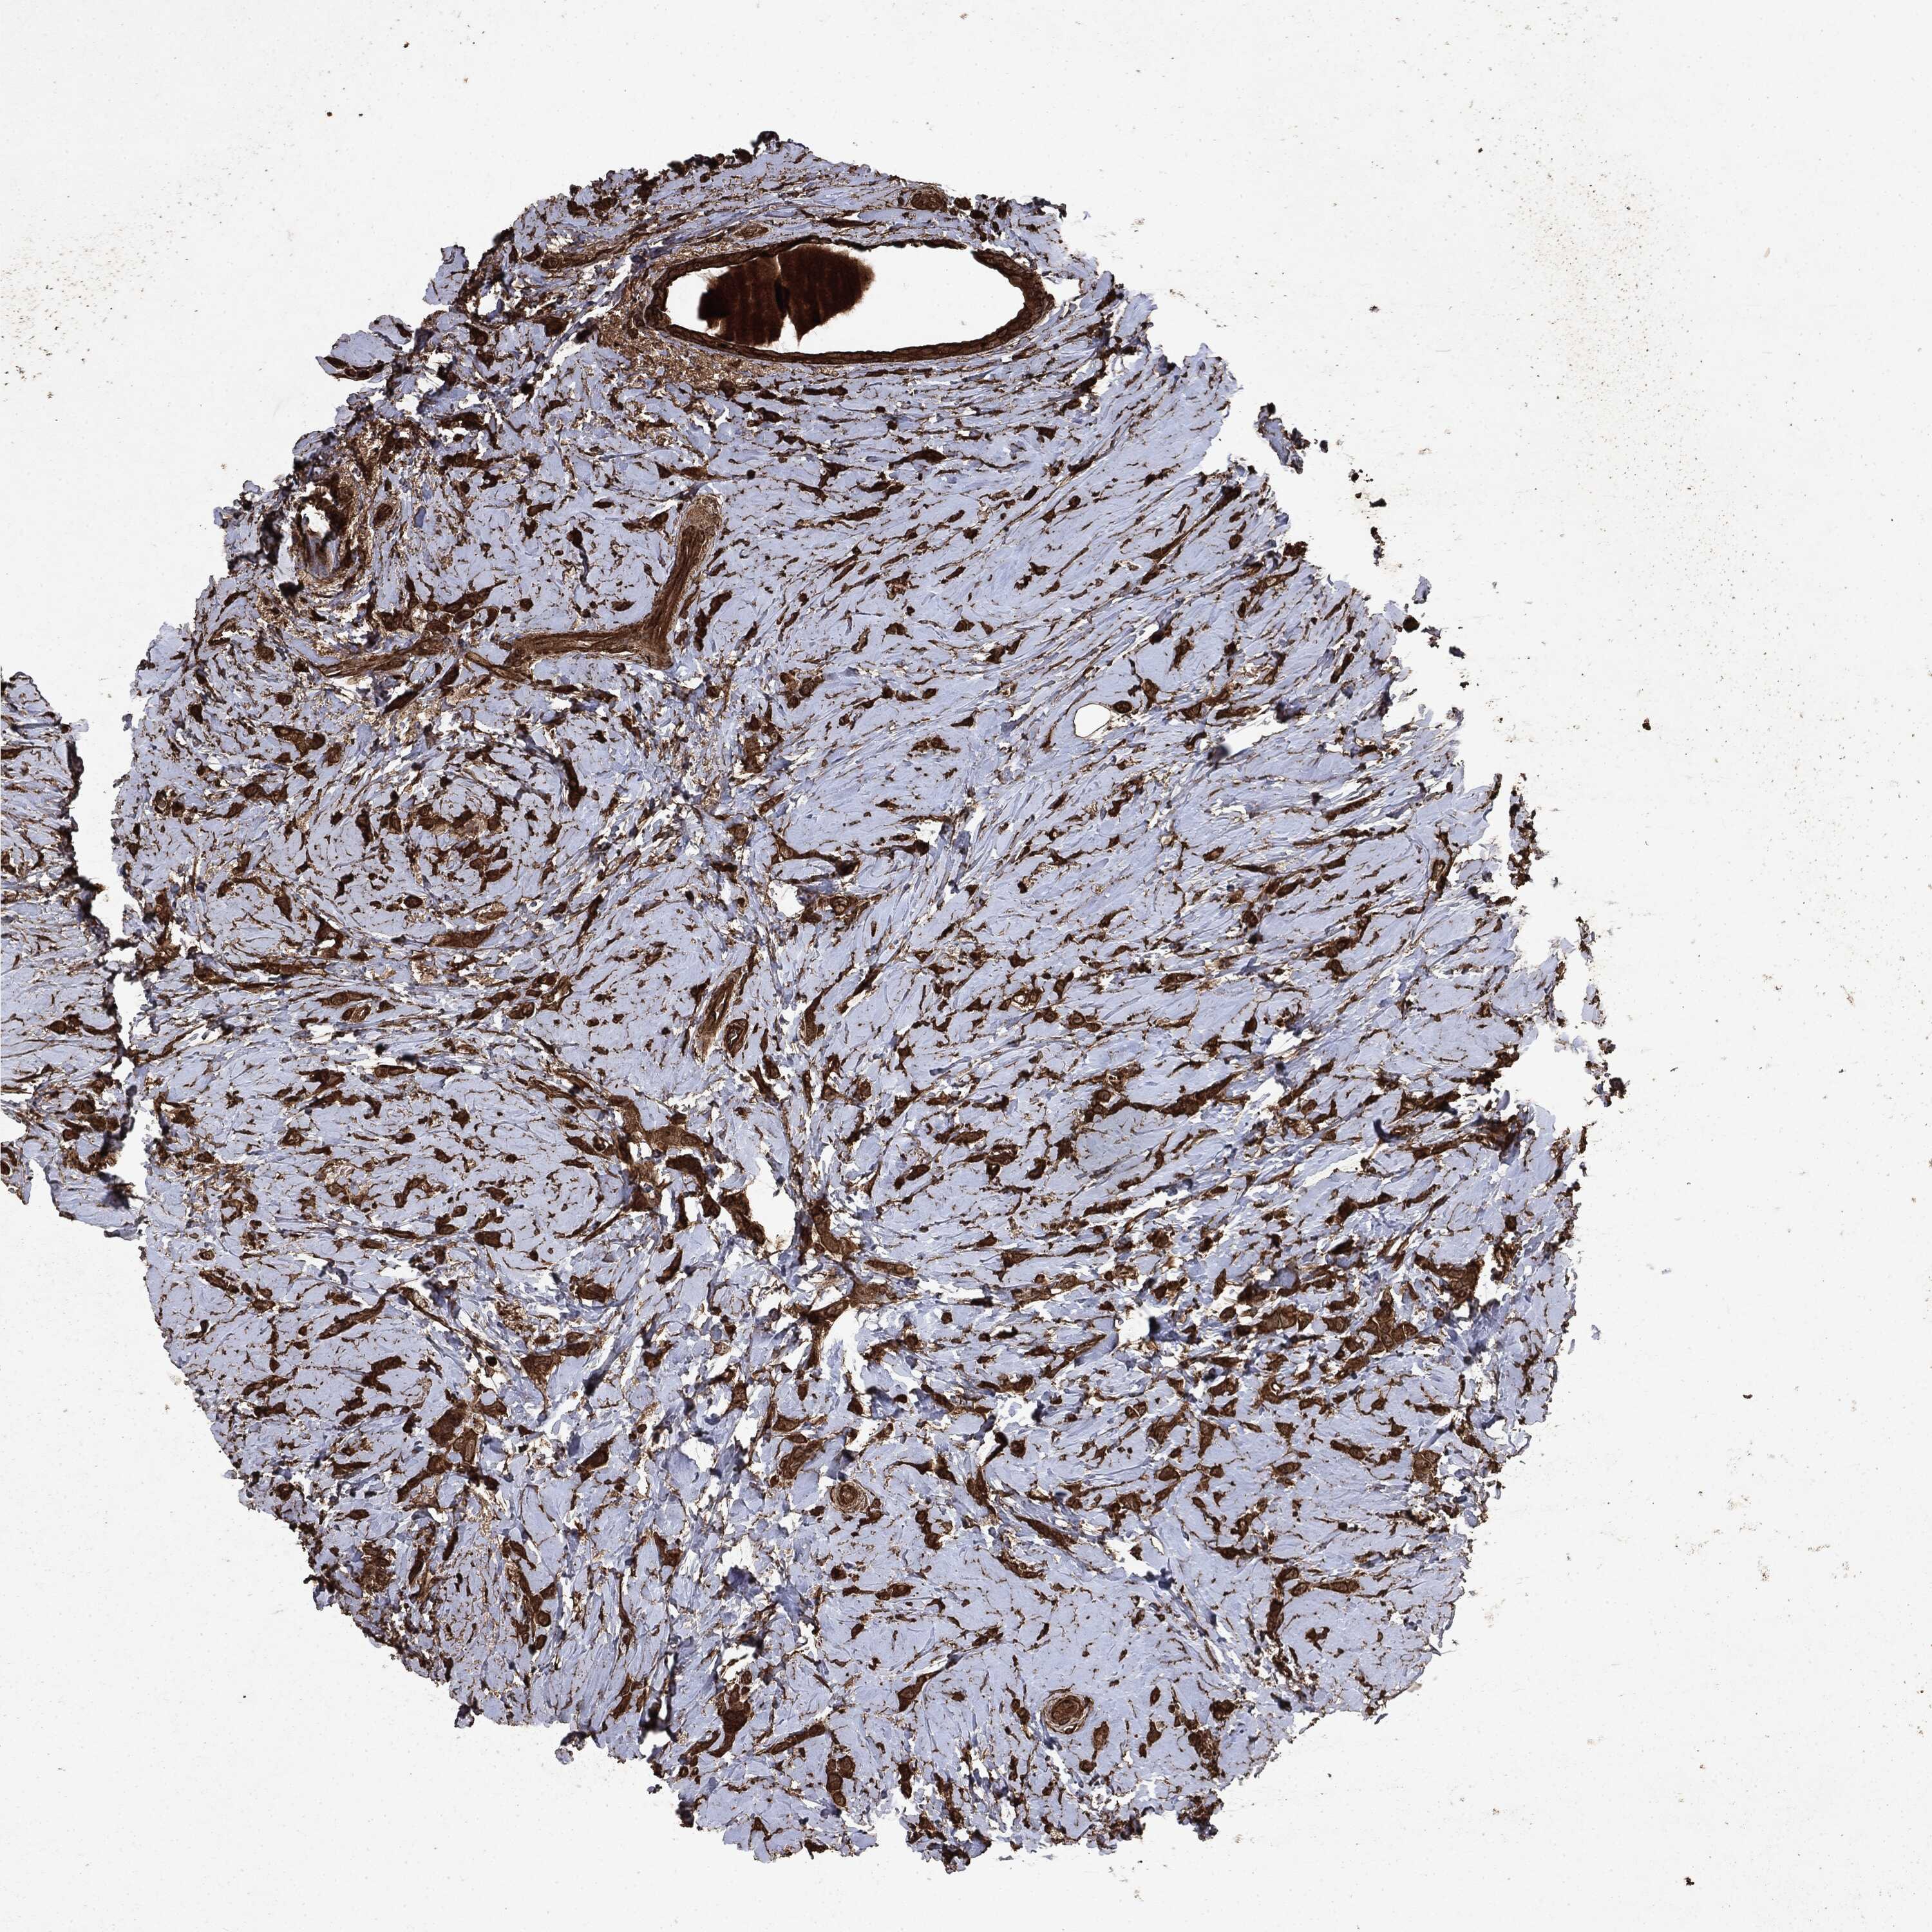

BRCA TCGA BRCA VALIDATION PROTEIN EXPRESSION

ANTIBODIES

AND

VALIDATION